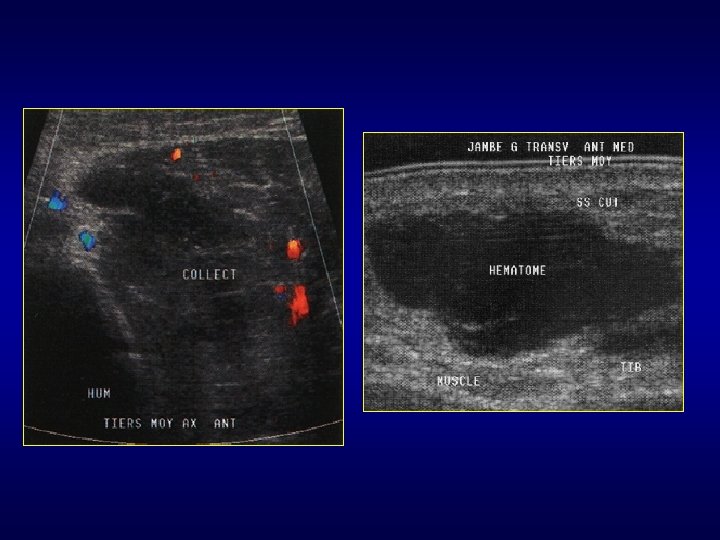

Est-ce vraiment un processus expansif? • Pièges : muscle accessoire, hernie musculaire, lésion musculaire traumatique, ténosynovite, moignon d’une rupture ligamentaire, hernie digestive, bursite, corps étranger en particulier plantaire, abcès (ddf avec tumeur nécrosée difficile +++), hématome (parfois ddf difficile avec T peu vascularisée), récidive post-op ou lymphoedème?